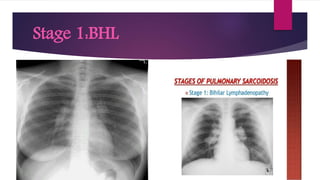

Chest X ray

 By convention thoracic sarcoidosis is classified in four (04) stages on the basis

 Stage I:Represents bilateral hilar lymphadenopathy

Stage 1:BHL